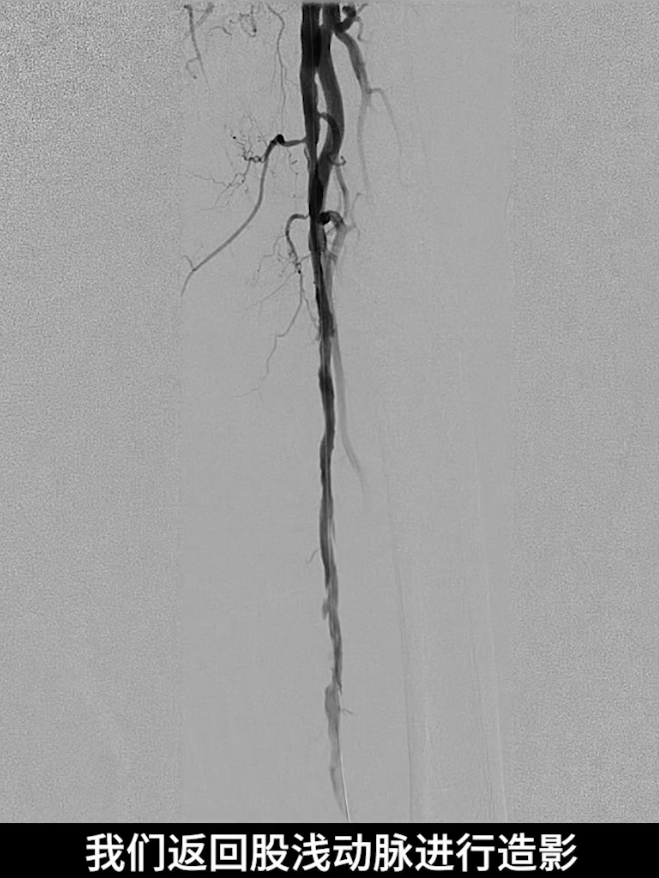

膝下流出道开通后,再次造影评估股浅动脉病变段,显示预扩张后存在多发夹层。

引入5.0×200mm紫杉醇涂层约束型球囊,对股浅动脉病变全程进行扩张,扩张时间维持5分钟。

术后造影验证:股浅动脉管腔恢复通畅,无明显残余狭窄,局限夹层未对血流造成影响,无需植入补救性支架;膝下腓动脉流出道通畅,胫后动脉至足底动脉血流连续,足部血流灌注显著改善。